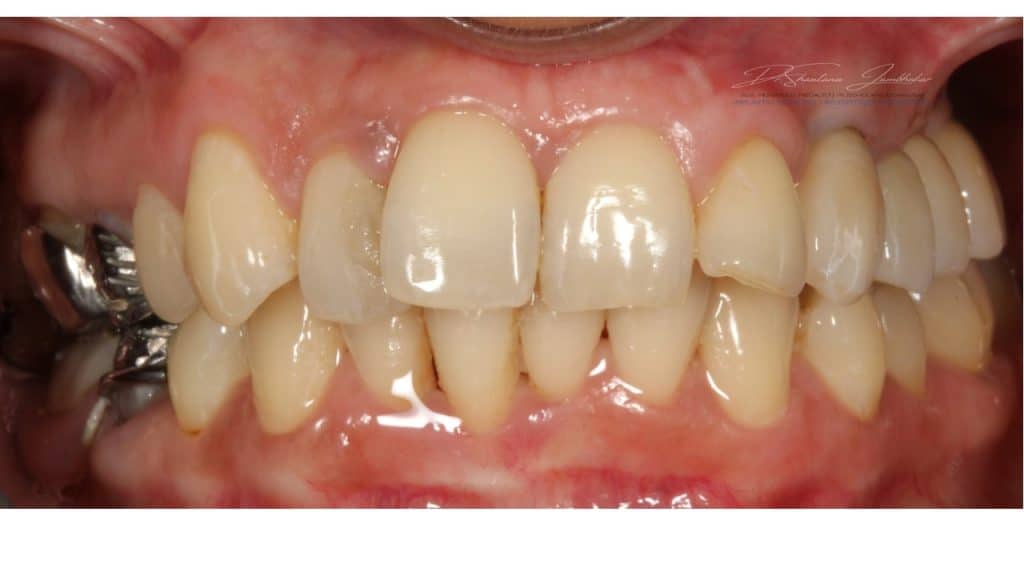

Cement retained Monolithic Zr Implant Restorations with 23 & Screw retained Monolithic Zr Implant restorations using Ti-base abutment with 24-25-26

Post treatment at 2 weeks

Post treatment image at 12 months followup

Post Treatment Follow up at 22 months